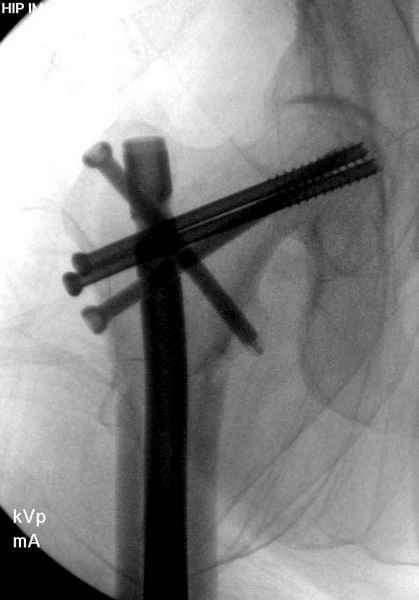

Профилактику дальнейшего раскола неполного перелома шейки провели тремя канюлированными шурупами.

На второй день после выписки упал дома. Снимки приложены. Коллеги рекомендуют удаление шурупа и вытяжение. Что делать?